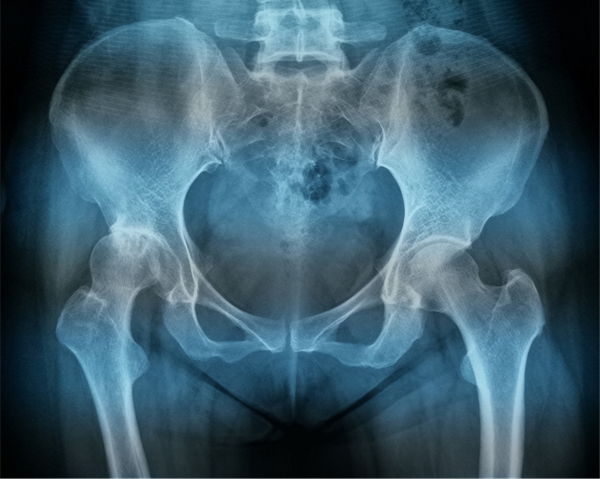

为了解除母亲的病痛,刘阿姨的女儿带着她来到ac米兰官网中文网站一院,找到了毕郑刚和耿硕团队。经过细致的问诊、查体和相关影像学检查,毕郑刚和耿硕发现刘阿姨患有髋关节发育不良,从而导致了髋关节的重度骨性关节炎,这种情况可以通过全髋关节置换手术来治疗。

骨科关节置换手术,术前精准手术方案的制定是手术成功与否的关键。手术前,耿硕根据患者术前三维CT扫描数据,进行三维术前规划,精确测量患者相关参数,计算适合患者假体型号及测试假体安放位置,实现个性化定制手术方案,经过术前规划,刘阿姨右侧髋关节应当采用54mm G7髋臼杯,11号ML taper股骨柄,这套方案适合刘阿姨的生理解剖,使术后功能更加良好。